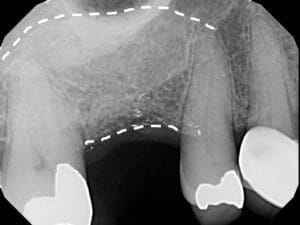

Ridge Augmentation

Sometimes the bone is severely reduced by trauma, infection or extended time without a tooth. When this occurs, that bone needs to be rebuilt in a process called Ridge Augmentation. For this, bone graft materials must be placed under the gum tissue and shaped into the form of the original bone. A dissolvable membrane is used to keep the bone graft protected. Sometimes, biological growth factors may be added to enhance the bone growth. Dr. Kuznia and Dr. Storch typically wait between 4 and 6 months before augmented bone is ready to hold a dental implant.